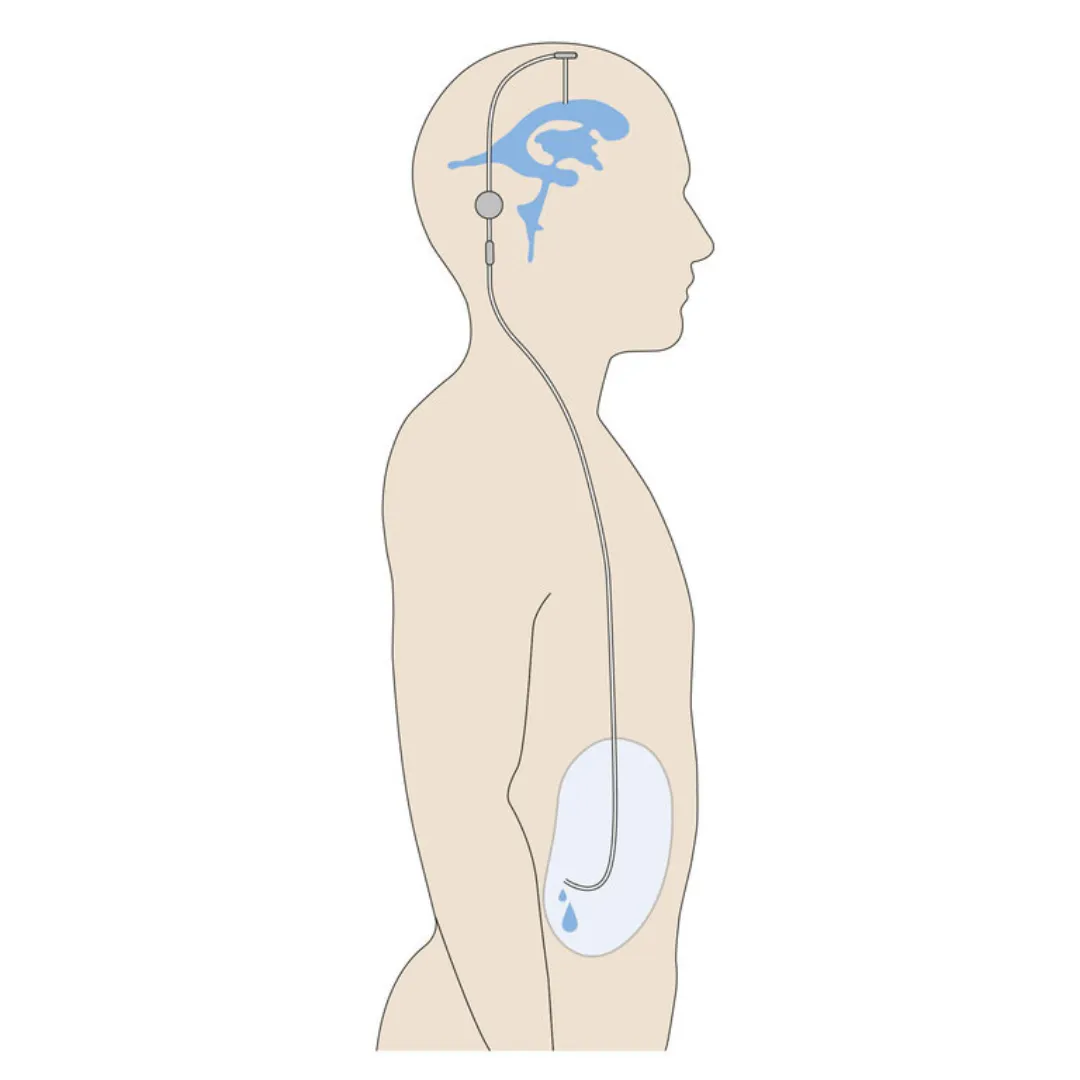

Advanced Drainage

Advanced Drainage

Hydrocephalus Management

Placement of ventriculoperitoneal (VP) shunts to regulate intracranial pressure and divert excess cerebral fluid safely.